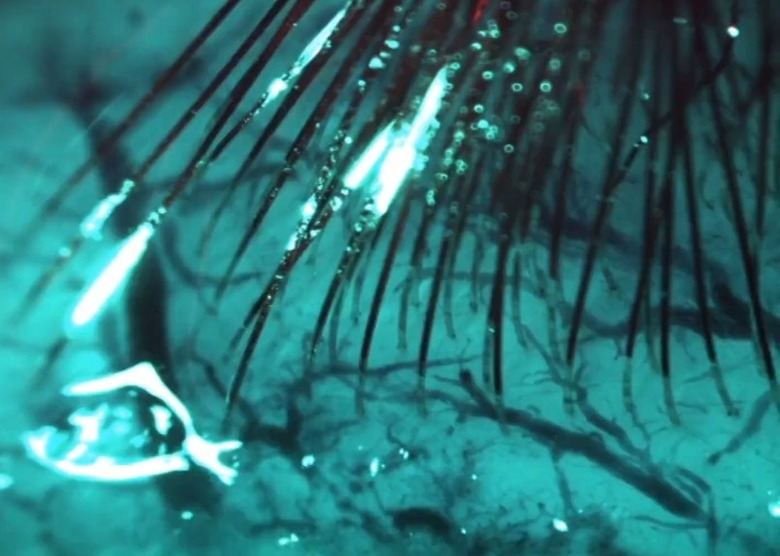

According to the article, its bundles of flexible threads are about one quarter the diameter of a human hair, implanted using needles to avoid blood vessels on the brain's surface. Then the embedded sensors capture information and send it to a receiver (the chip above) on the surface of the skull. From there it transmits wirelessly — Elon Musk said it could Bluetooth the information to your skull. Right now implantation requires drilling holes, but researchers hope in the future they can use lasers to avoid "unpleasant" vibration.

Neuralink president Max Hodak went on to explain why it's embedding sensors directly into the brain, near but not in neurons. Simply, it's the only way to send and receive the information necessary, from "spikes" of activity. A neurosurgeon is also part of the presentation, showing off some videos of the implantation technology, and how its robot can install thousands of wires directly into the brain while avoiding tissue damage and bleeding. Eventually, they'd like to do it without shaving the patient's head, although he acknowledged that the first operations will be more like current deep brain implants.